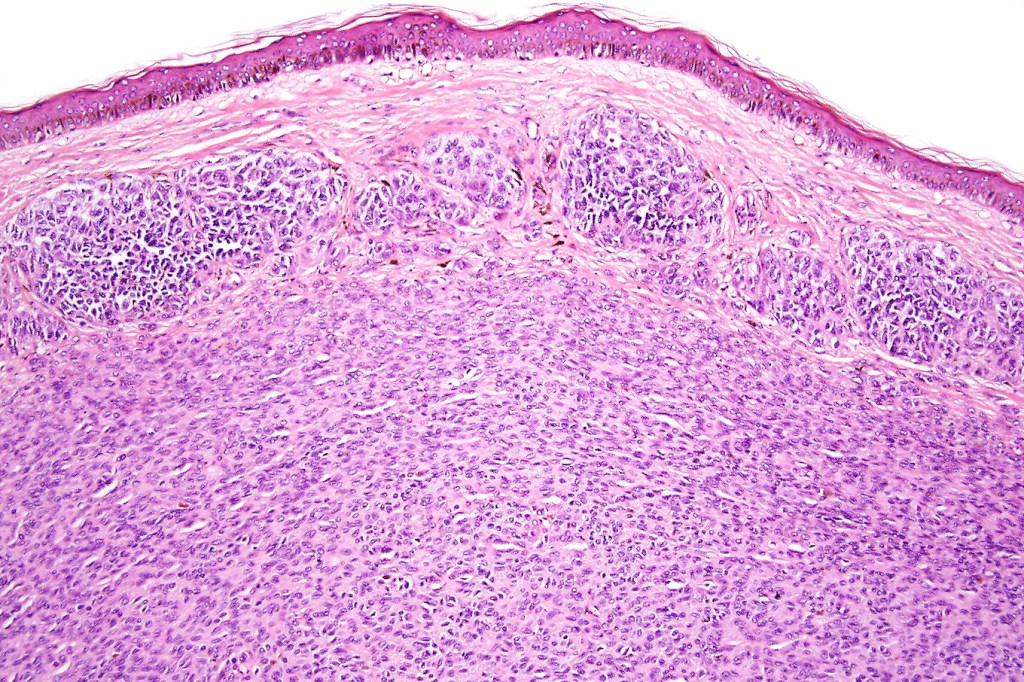

•Absence of necrosis, hemorrhage or Pagetoid spread in the overlying epidermis

•Spindle cell, small blue cell, blue nevus-like features, Spitzoid & proliferative nodules with mesenchymal differentiation (myofibroblastic, chondroid & osteoid) can be seen